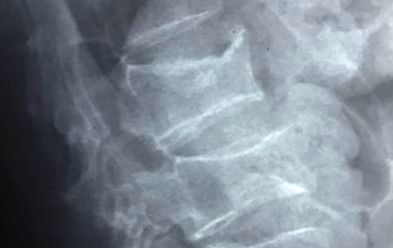

Varón de 39 años que consulta por alteración visual (hemianopsia bitemporal)

Imagen osteolítica de cráneo vinculada a enfermedad de Paget